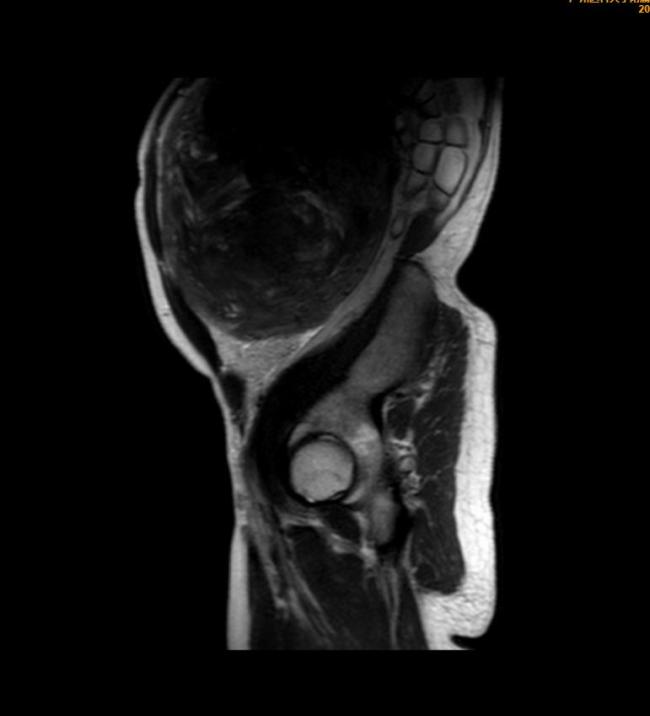

52岁的王女士腹部隆起,看起来像是即将临盆的产妇。她最近去医院检查时才发现,10年前查出的子宫肌瘤已经悄悄长到近30厘米,接近一个篮球那么大。

10年前,王女士体检时发现子宫肌瘤大小约4厘米,像个小土豆。多年来,她没有感到明显不适,便没有在意,十年间从未复查过。直到最近,因严重便秘影响生活,她才到医院检查,发现子宫肌瘤已经长到近30厘米。

若再放任肌瘤继续生长,可能会出现经量增多、经期延长导致严重贫血,也可能出现肿瘤压迫症状如尿频、便秘等,最重要的是有恶变的风险。医院团队为王女士实施了开腹全子宫切除术,切下来的子宫约莫有一个“篮球”那么大,重达4公斤。术后,王女士恢复良好,第四天就顺利出院了。